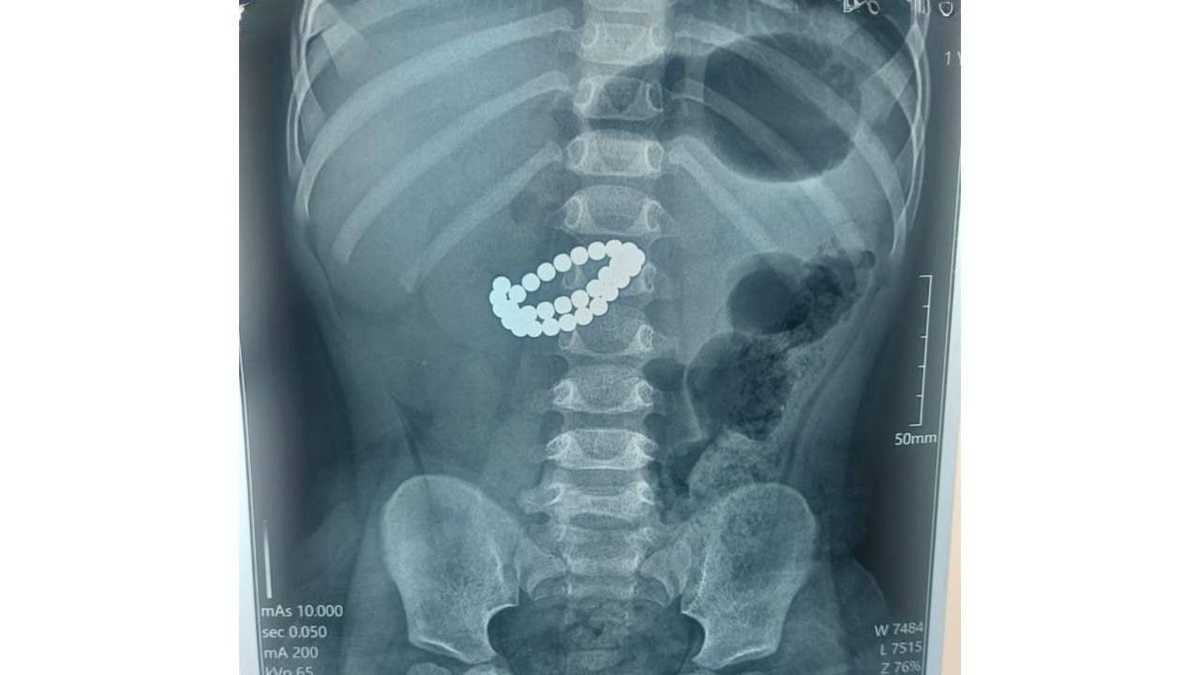

Алматы: врачи спасли двухлетнего ребёнка, проглотившего 31 магнит

Двухлетний мальчик поступил в больницу в критическом состоянии; при обследовании в кишечнике обнаружили 31 магнит. Хирург Аскар Ризванов пояснил: «попадая в организм по отдельности, магниты притягиваются уже внутри кишечника, сдавливают его стенки и могут за считанные часы вызвать перитонит».

Медики провели оперативное вмешательство и извлекли все магниты, спасая жизнь ребёнку.